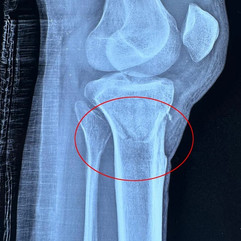

Volar Barton fracture of the left distal radius Before Surgery